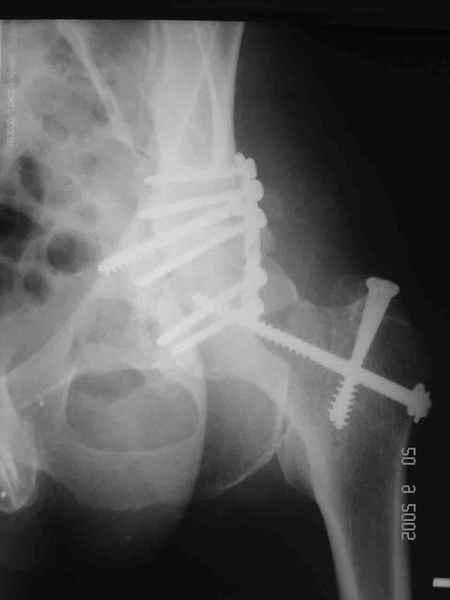

Привет! Вот недавно прооперировали похожий на ваш случай - впадина + шейка (правда у нас впадина поперечный+задний край). После травмы прошло 4 недели. мужчине 46 лет. С такой комбинацией все показания к первичному протезированию. Морально и технически мы к этому уже созрели.Но больной не собрал денег на протез. Выполнили остеосинтез впадины и шейки, прекрасно понимая, что головка вскоре рассосется, мы хотя бы надемся что к этому времени таз срастется, как говорится создали все условия для дальнейшего протезирования (может, и протез в последующем подешевле будет, в смысле, без укрепляющего кольца?). Привет Рункову!

Рунков 27 Сентябрь 2005, 09:57

Привет Алекей! Сделано неплохо, поздравляю, хотя второй винтик можно было бы и подлиннее в шейку загнать! Пара вопроов: доступ такой же? головка была свободной или висела на капсуле?

Согласен, можно было и подлиннее. Доступ такой же - чрезвертельный, только разрез кожи прямой (а не Y, чего то я разницы не ощущаю). Головка была абсолютно свободной (то есть во время остеосинтеза таза лежала в стакане и не мешалась). Шансов, что она прирастет 0,00001%. Хотели даже выбросить, но привинтили как временный биологический протез (читай свободный трансплантат), чтоб на период срастания таза бедро проксимально не ушло (может ортопеды потом спасибо скажут). Ну а у вас первичное протезирование при переломе впадины тоже пока полько в планах?